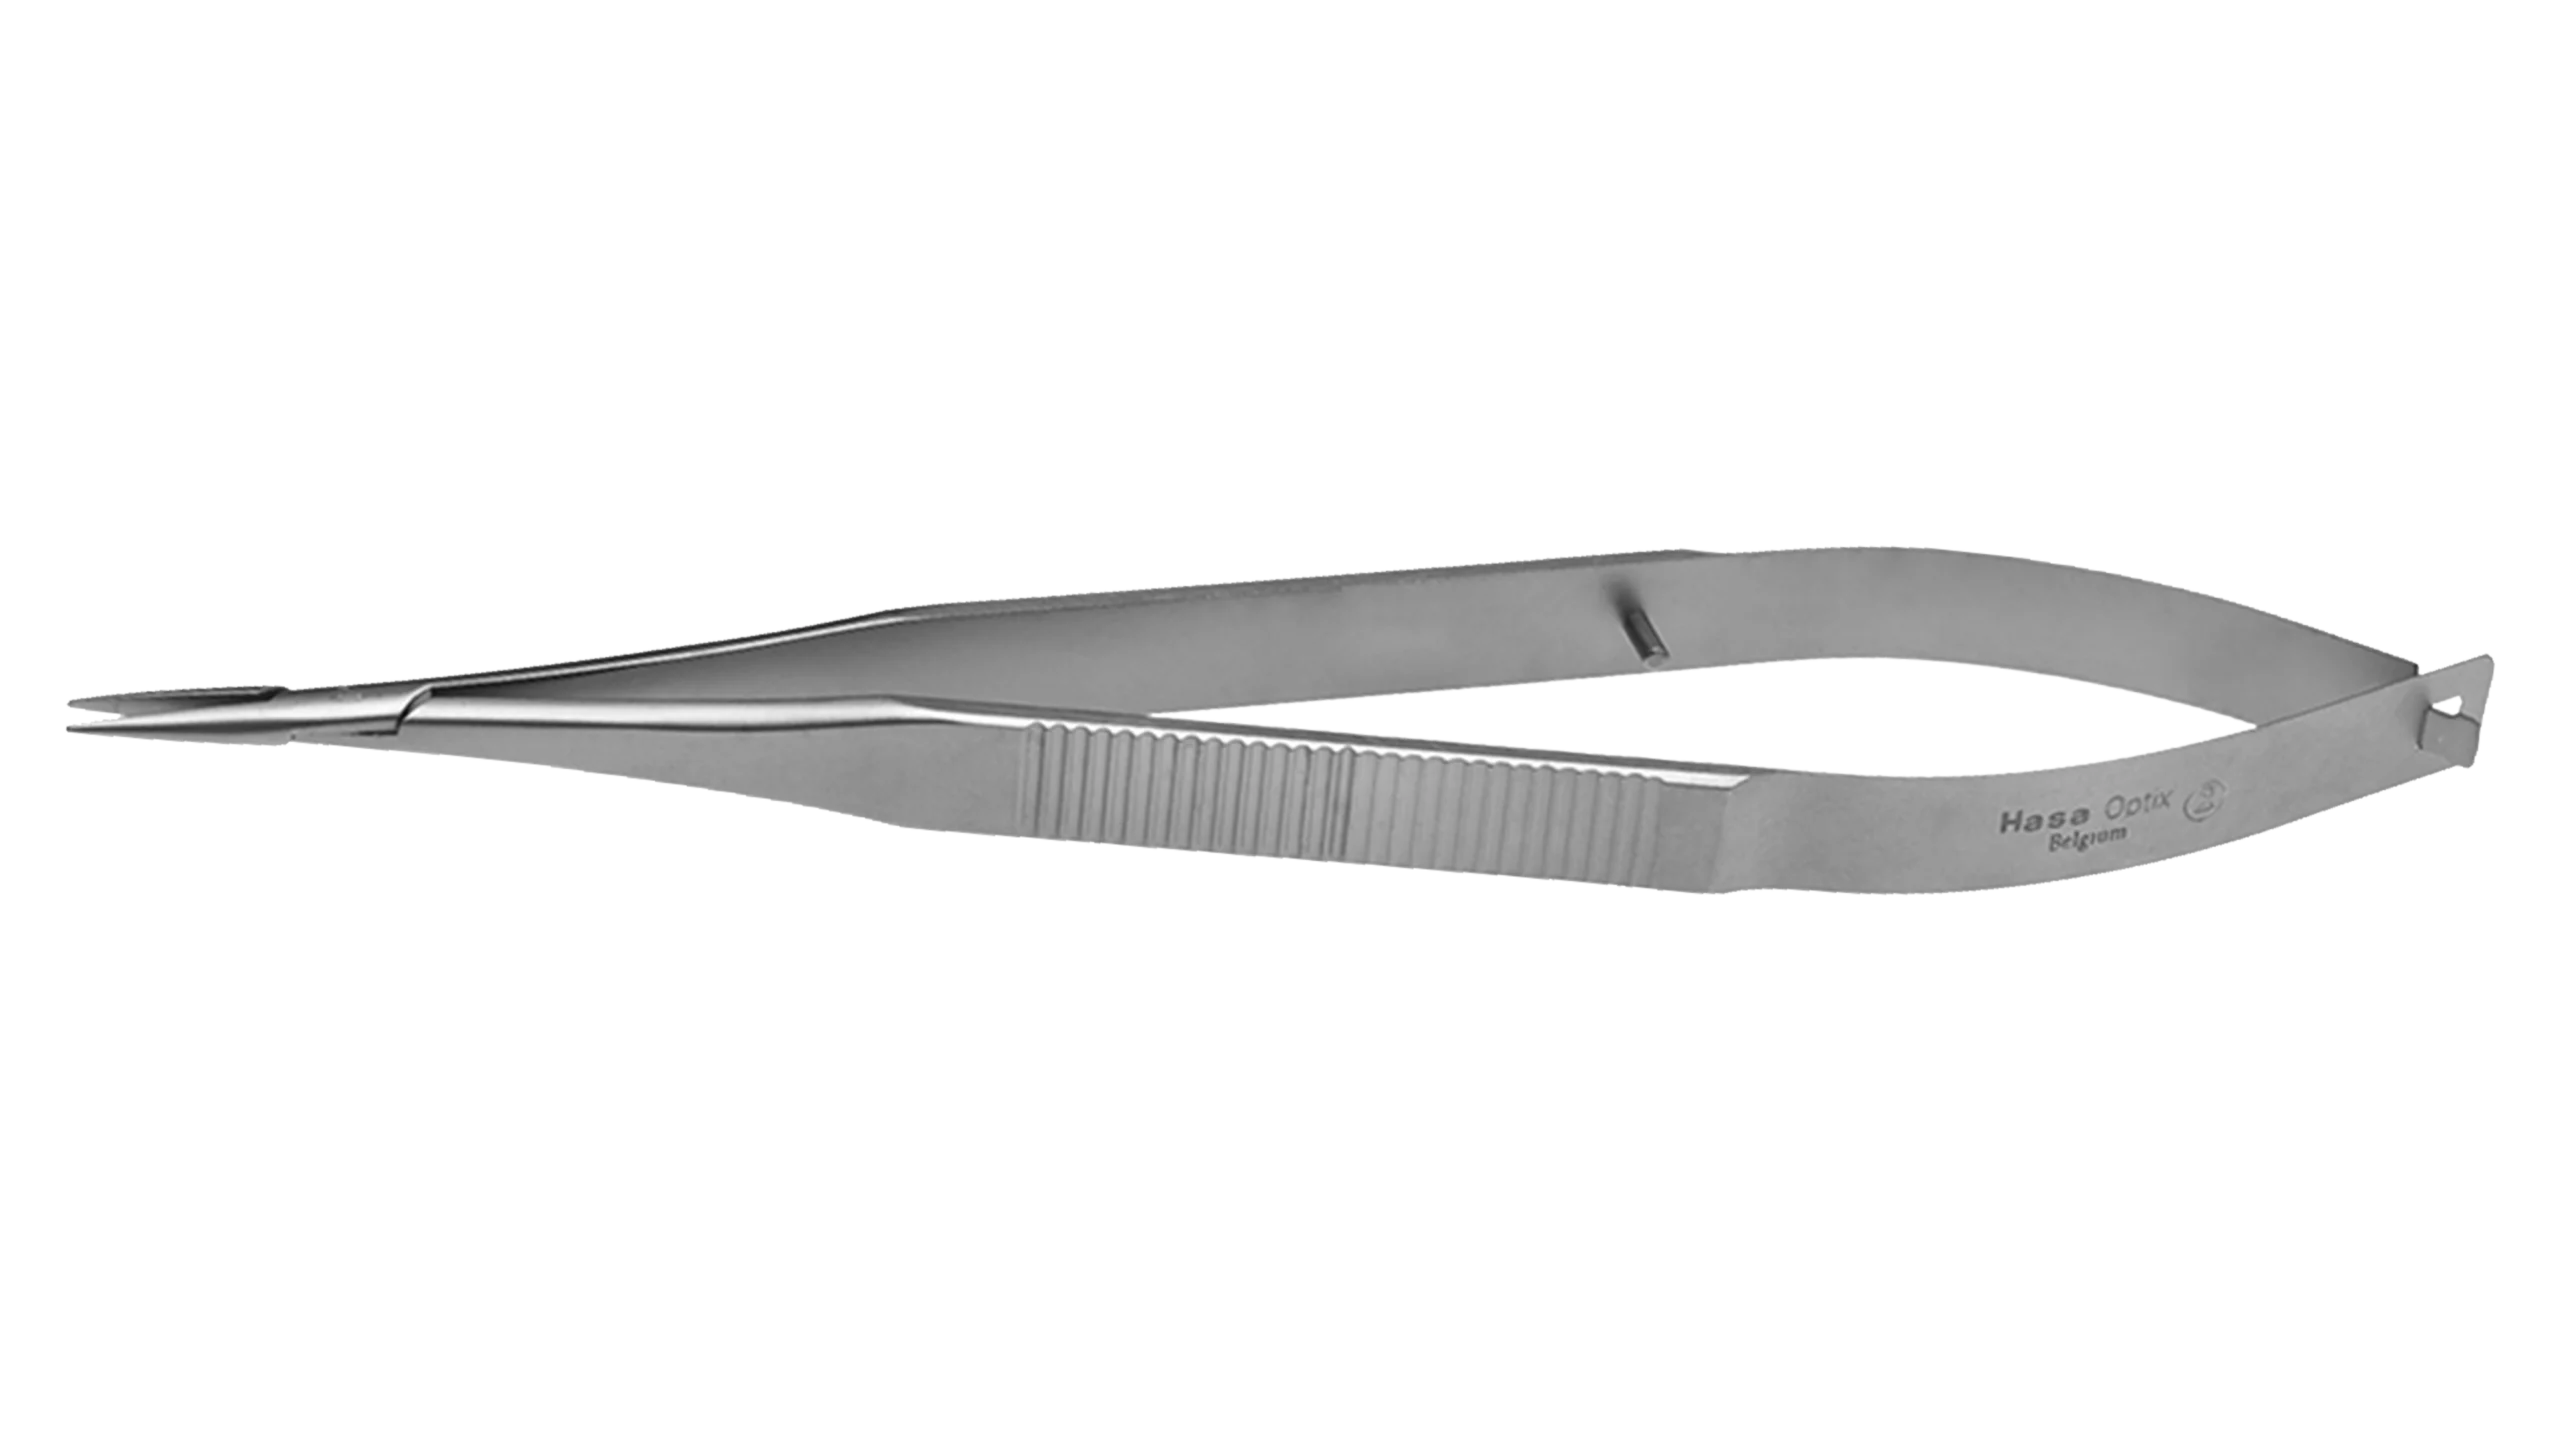

Ophthalmic Surgical Instruments

Wide range of recyclable ophthalmic surgery instruments.